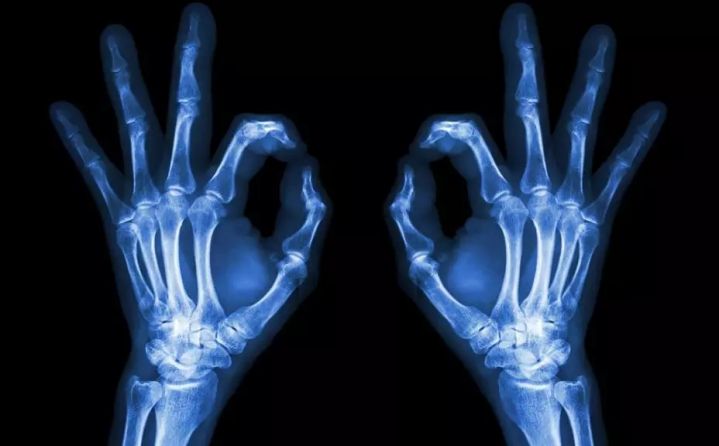

1、外伤骨头——粗看X光片、细看CT

各种外伤,如果怀疑伤到了骨头,优先选择X光照片,检查结果快速易得。若要进一步观察,可以选择CT。超声、核磁对于骨皮髓质等看不大清,一般不选择。